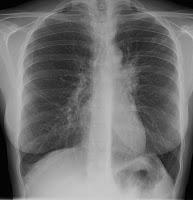

explicar por qué la gran mayoría de las personas infectadas con el Mycobacterium

tuberculosis (Mtb) pueden tolerar la infección sin desarrollar la enfermedad.

El equipo descubrió que, en lugar de luchar para resistir el patógeno, la

tolerancia del cuerpo a Mtb es el mecanismo clave para prevenir la propagación

de la infección. Encontraron que tener niveles excesivos

de células T, podría causar más daño que